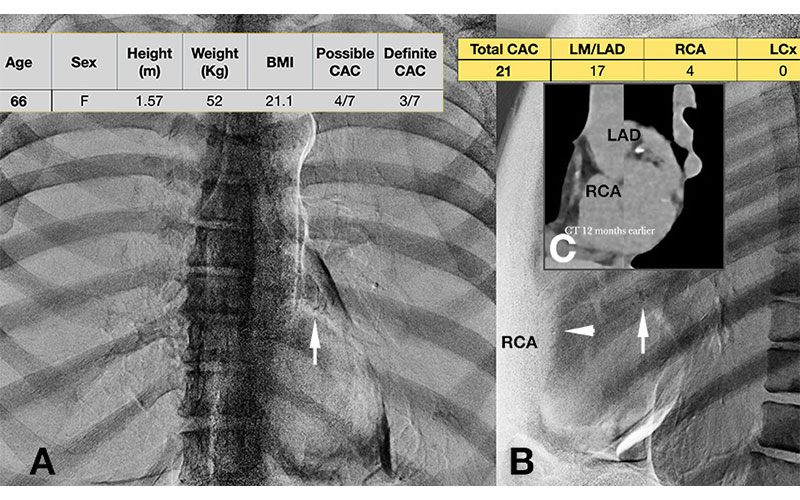

CT Improves Cardiovascular Risk Assessment in Women with Chest Pain

Quantifying plaque may help catch women with high risk who may be missed by traditional models

Chest X-Rays Offer Second Look for Heart Disease Risk

Dual-energy lateral images help radiologists spot coronary calcium and could support earlier prevention